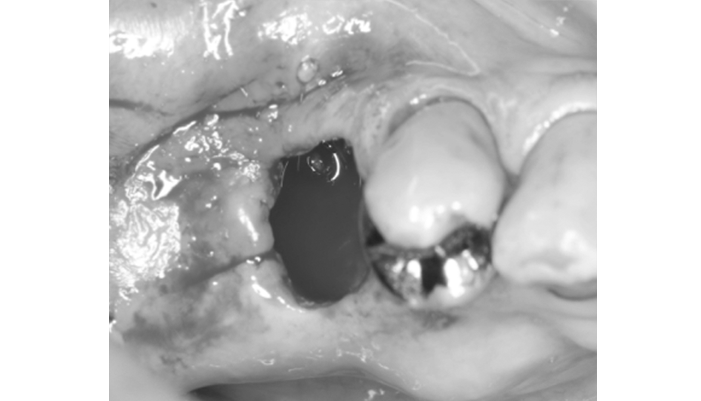

歯牙移植の症例

症例1

治療前

治療後

治療の経緯

患者様は「抜歯しかないと言われた」とのお悩みで来院されました。診査の結果、保存が難しい歯が確認されましたが、親知らずの状態が良好で移植の条件を満たしていました。そこで、自身の歯を活用する治療として自家歯牙移植を行いました。

| 主訴 | 歯が痛く、腫れている |

|---|---|

| 治療期間 | 3〜4ヶ月 |

| 治療費 | ¥110,000(税込) |

| 治療内容 | 右下奥歯が割れているため抜歯となりました。親知らずが残っていたため、抜歯後に親知らずを抜いた場所へ移植しました。 |

| 治療のリスク | 上手く生着しない(くっ付かない)ことがあります。 |